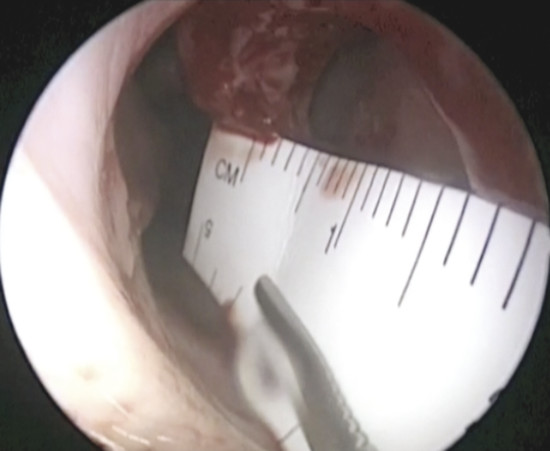

In addition, it is possible to measure the size of the NSP under endoscopic control that is critical when choosing the most suitable surgery (Fig. 6‑4).

The disposable paper ruler found in some surgical pen packs can be trimmed and introduced into the nose to obtain an accurate measurement. If this instrument is not available, the graduated end of the Cottle septum elevator can be carefully inserted and slid against the septum to determine the size of the NSP.